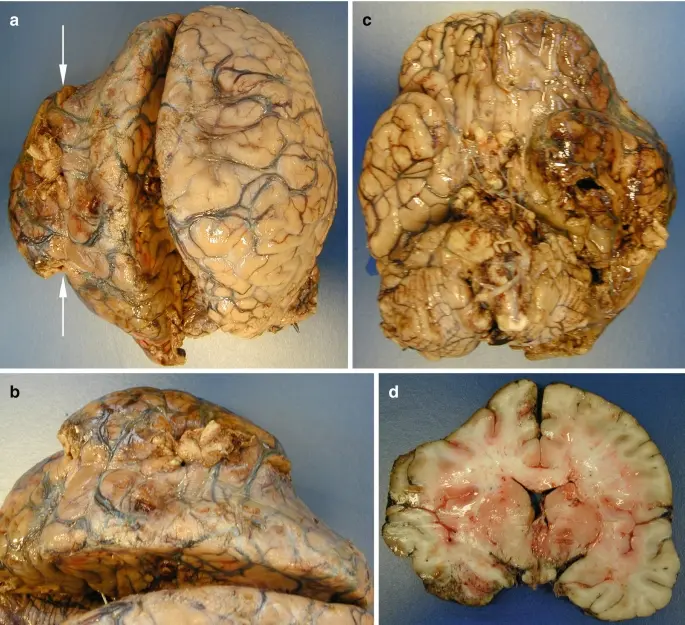

1.Complete memory loss - a life without clarity

The neural pathways in the brain become so damaged that no supplement can help. The person permanently loses their ability to recall memories. Relationships deteriorate. Confidence shatters. Depression takes hold. I've seen patients who isolated themselves at home, unable to face their loved ones.

2. Dementia - the silent thief

Untreated cognitive decline can evolve into dementia. It may start as occasional forgetfulness, but before you know it, the condition has spread, impairing judgment and daily function. Patients describe the mental haze as a fog they can't escape. Most are diagnosed too late-when little more can be done.

3. Brain fog leading to chronic fatigue

Inflammation spreads from the brain to affect overall neurological health. The result? A mind that slowly shuts down. Mental exhaustion becomes your new norm-struggling to think clearly, day after day, as your body weakens. I've seen individuals beg for relief that never arrives.

4. Stroke caused by impaired blood flow

Cognitive decline is often the first sign of poor vascular health-not just in the brain. If ignored, a clot could strike, causing a stroke. I've seen seemingly healthy 45-year-old individuals on the operating table, fighting for their lives, all because they assumed their "lapses" were just a part of aging.

5. Nerve damage and mental confusion

Chronic cognitive decline can destroy the nerves responsible for mental processing and focus. Suddenly, you lose control over your thoughts. Mental disarray becomes your daily reality-even at a young age. People tell me they're too ashamed to engage with others. This isn't an "old person's condition"-it can happen to anyone.

– The blood vessels throughout the body are closely connected. If the vessels in the brain are clogged with plaque, they receive fewer nutrients. That's where cognitive decline and other serious issues begin.

The same goes for the heart. People with cognitive decline are 59% more likely to develop coronary artery disease or atherosclerosis, and 34% more likely to suffer a stroke. As we've discussed, cognitive decline can also lead to depression, which further increases the risk of cardiovascular disease. Add in the overuse of Aricept, which negatively impacts brain function-and suddenly, the person suffering from cognitive decline is almost guaranteed to face fatal neurological complications.